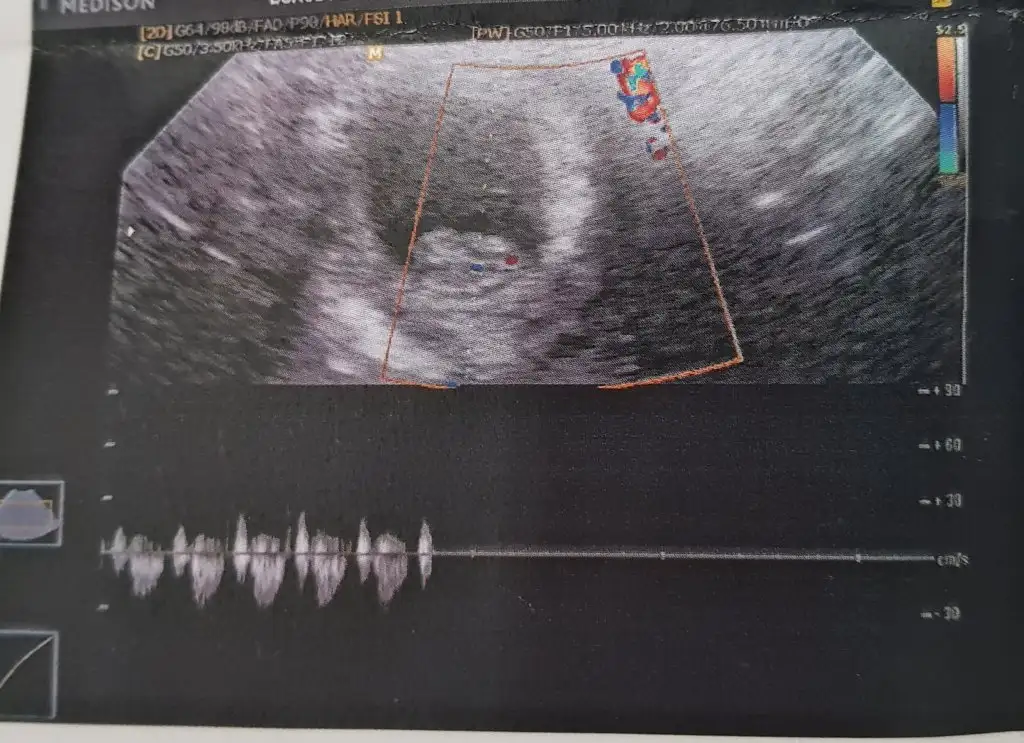

Arkadaşlar lütfen babada bakın kız mı erkek mi çok merak ediyorum 10haftalik bu resimde